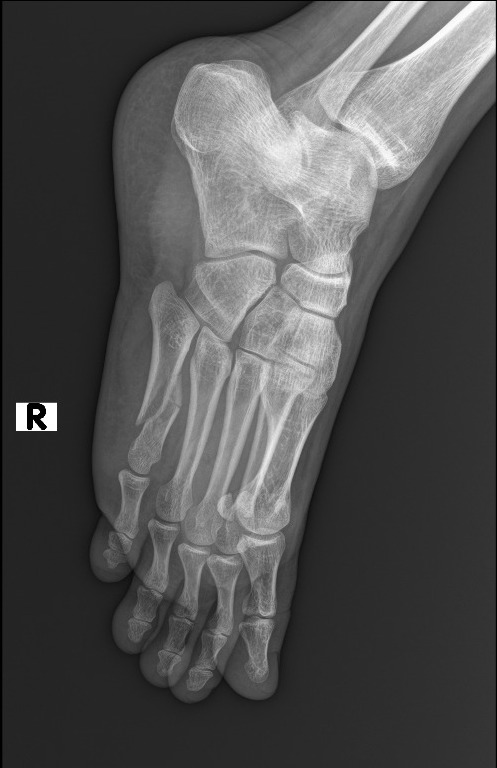

Mau liat rontgennya?

Patah tulang. Bagian metatarsal.

Diapain?

Operasi jam 10 malam, dipasang pen.